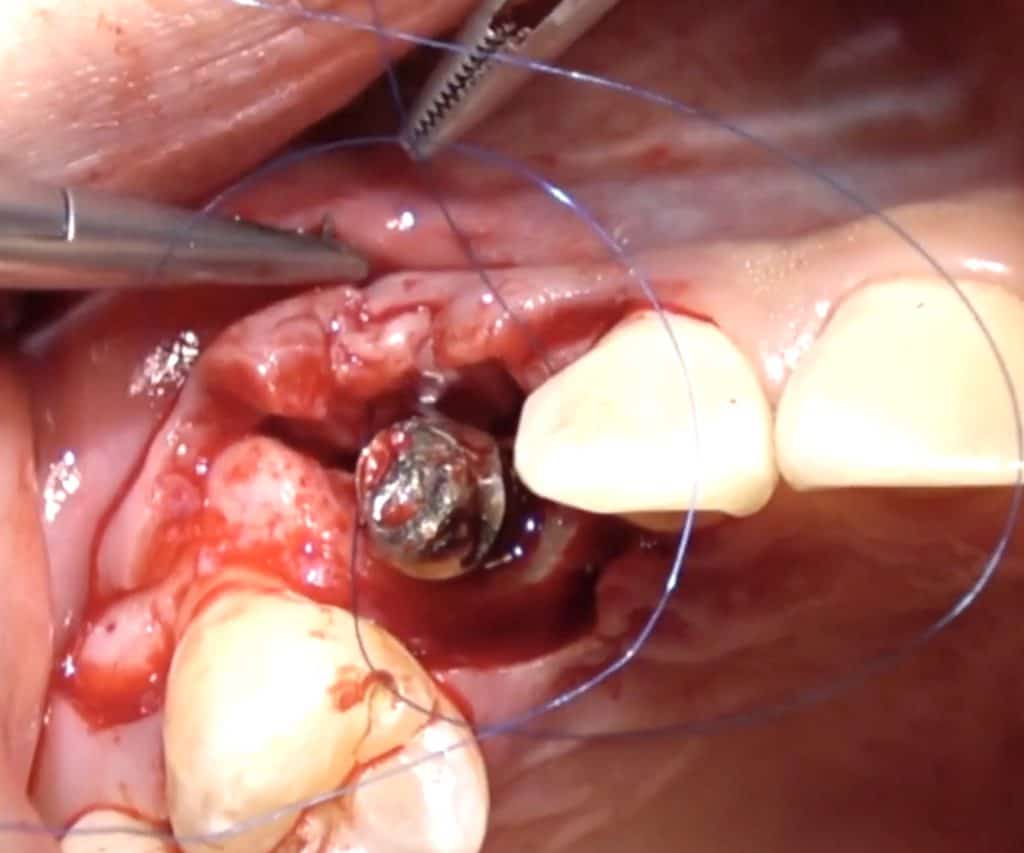

Here is a clinical video of a procedure where the CT-Epithelial graft is applied to create a 2-3 mm zone of keratinised mucosa buccal of an implant crown in the mandible. The graft is harvested from the palate and applied with the procedure explained before

Connective tissue grafts have been also proposed as part pf peri-implantitis surgeries and I think in certain cases they certainly have a purpose to fulfill. I have used the Hybrid CT-Epithelial graft often in peri-implantitis surgery, especially in cases with absence of keratinised mucosa and very thin peri-implant tissue. You can watch such a surgical case in our online Masterclass on the management of implant complications to the right!